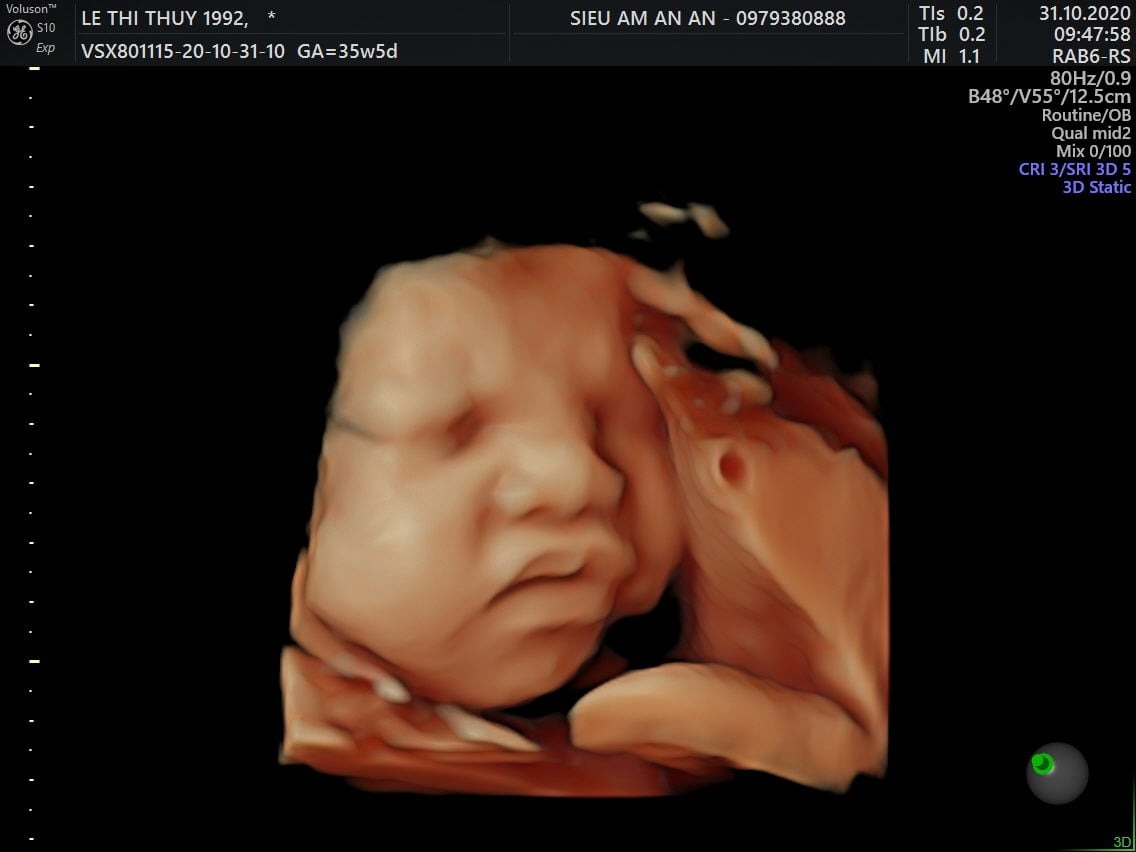

Sự phát triển của thai nhi 36 tuần tuổi

Tuần 36 cũng chính là dấu mốc quan trọng đánh dấu thời gian con chuẩn bị chào đời. Tuy là thế, mẹ bầu tuần 36 vẫn cần chú ý rằng, con vẫn sẽ có nhiều sự phát triển khác.

Kích thước thai to xấp xỉ bó cải, dài khoảng 47 cm, nặng khoảng 2,7kg.